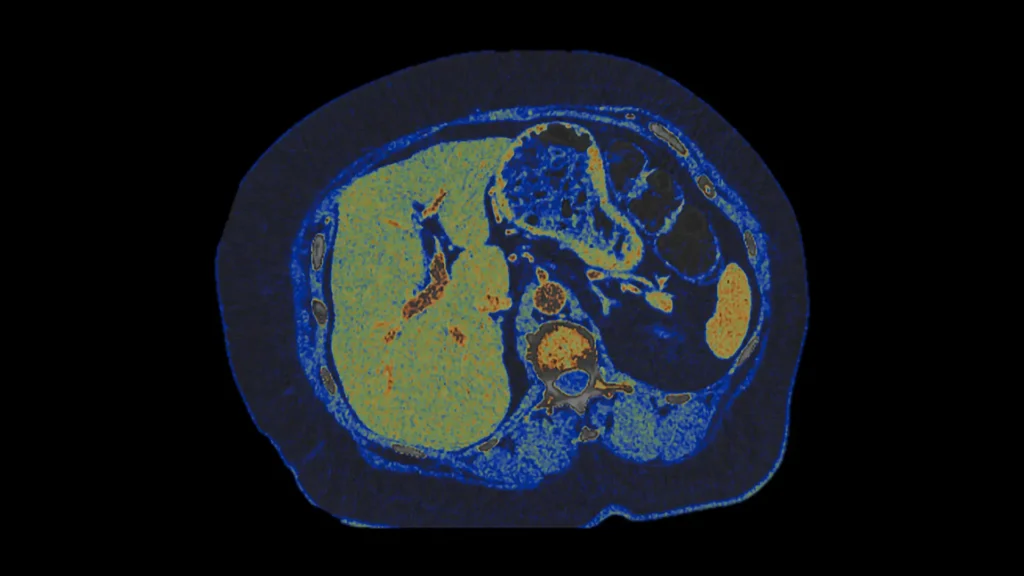

Photon-counting CT in oncologia

L’imaging spettrale a basso dosaggio può implementare la confidenza diagnostica nella valutazione delle lesioni tumorali primarie e secondarie fornendo una migliore assistenza ai pazienti.